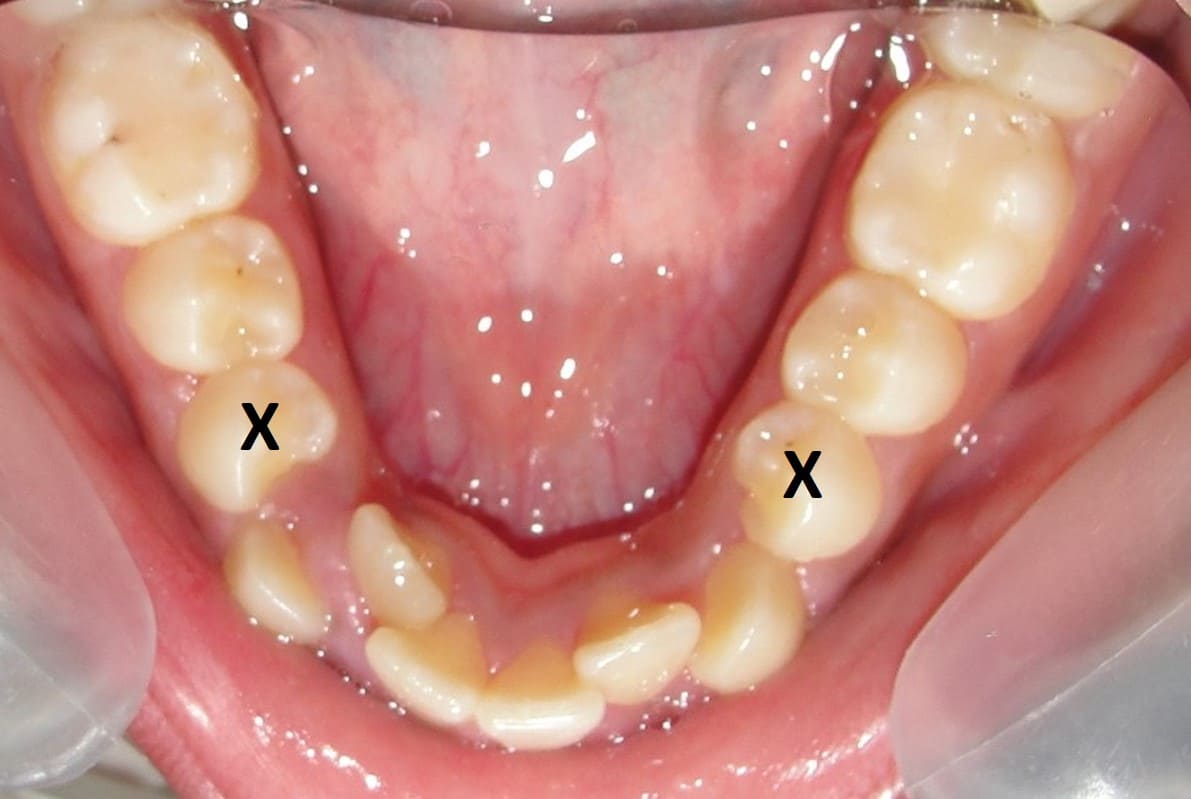

ولفت استشاري زراعة الأسنان وتجميل الفم، إلى أن عدم الزراعة الفورية للأسنان عقب الخلع يعرض الفك للعديد من المشكلات منها انكماش عظام الفك، بجانب حدوث مشكلة في مفاصل الفك.

- فقدان أو تلف الأسنان تماما.

- تمنع زراعة الأسنان فقدان أو ضمور العظم في مكان السن المفقود.

- تبقي على سلامة الأسنان الطبيعية المتبقية وتقويتها وتوفير الدعم للأسنان ككل.